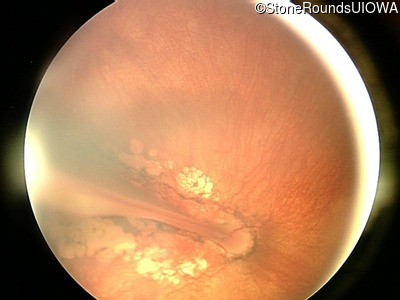

Fundus Photography - Right - 20/250

Exemplar